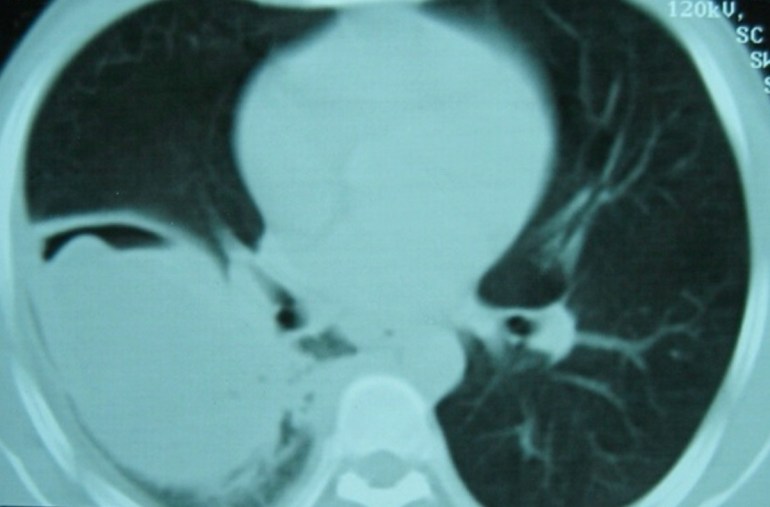

Not so much a clinical but a radiological vignette – a CT image from more than a decade ago.

Question: What is the radiological sign and what is the diagnosis?

The CT cut of the lungs shows a “water lily” sign (and thanks for those who suggested that it is an ugly or atypical “water lily”), which is almost diagnostic of a pulmonary hydatid cyst. This patient was seen more than a decade ago when I was in Peru for the famous Gorgas Diploma Course in Clinical Tropical Medicine. I cannot recommend this course highly enough, and there are now quite a number of distinguished alumni from Singapore.